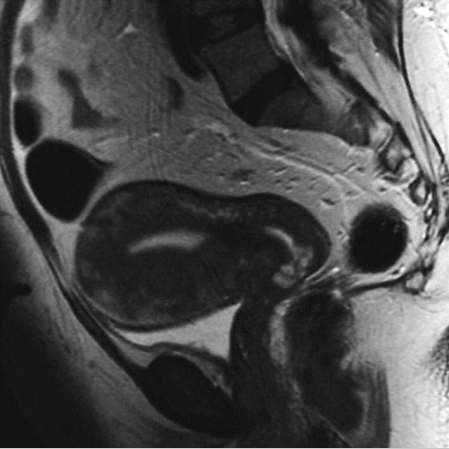

子宫腺肌病MR